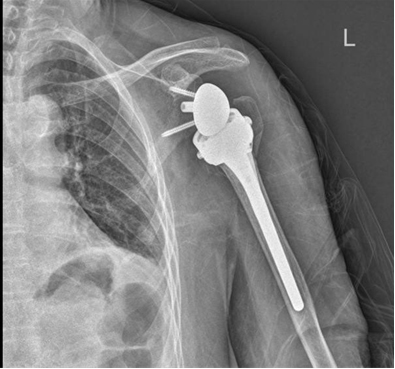

患者术后影像